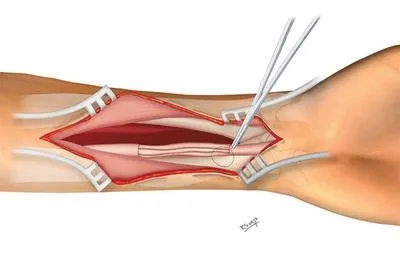

El Dr. Francisco González-Llanos es un neurocirujano reconocido internacionalmente por su dominio en bypass extra-intracraneales, revascularización cerebral compleja y cirugía de base de cráneo.

Su experiencia incluye también toda la amplitud de la cirugía de columna, desde técnicas mínimamente invasivas hasta reconstrucciones y artrodesis de máxima complejidad.

Director del Curso de Microcirugía Cerebral‑Vascular y Bypass Extra‑Intracraneal (desde 2006, Hospital La Paz).